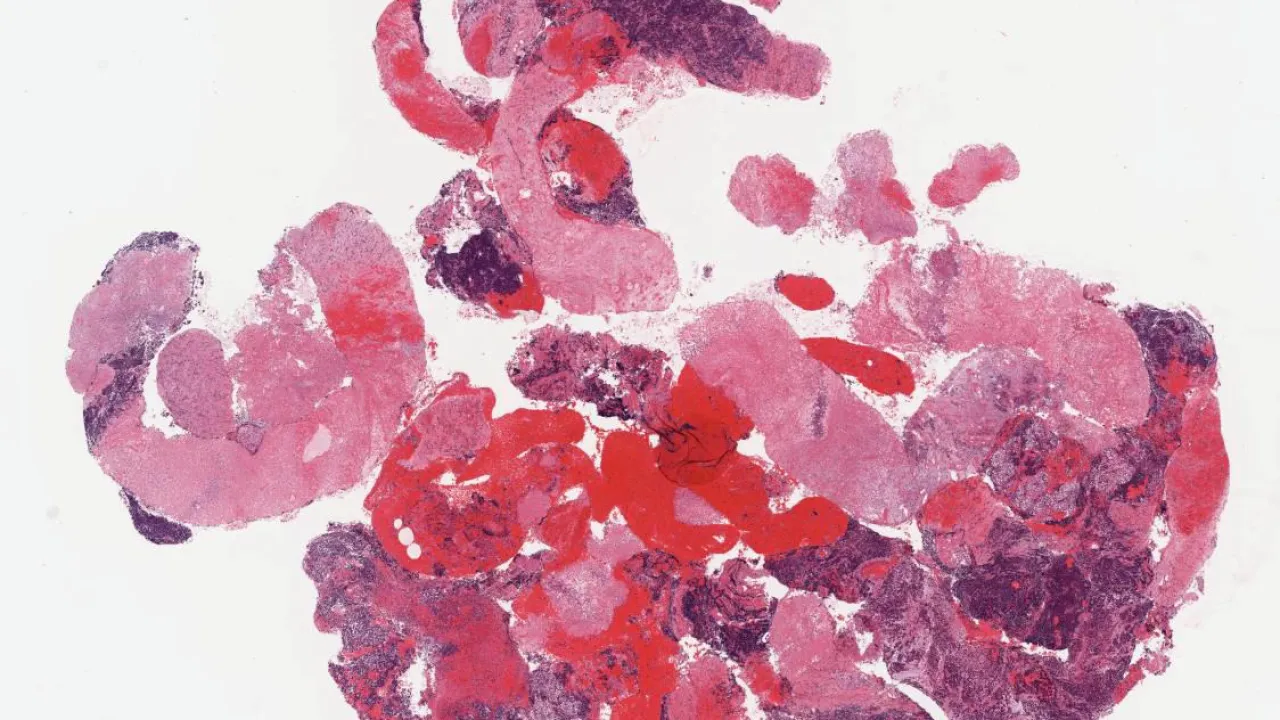

Soft Tissue, Adenomatoid tumour